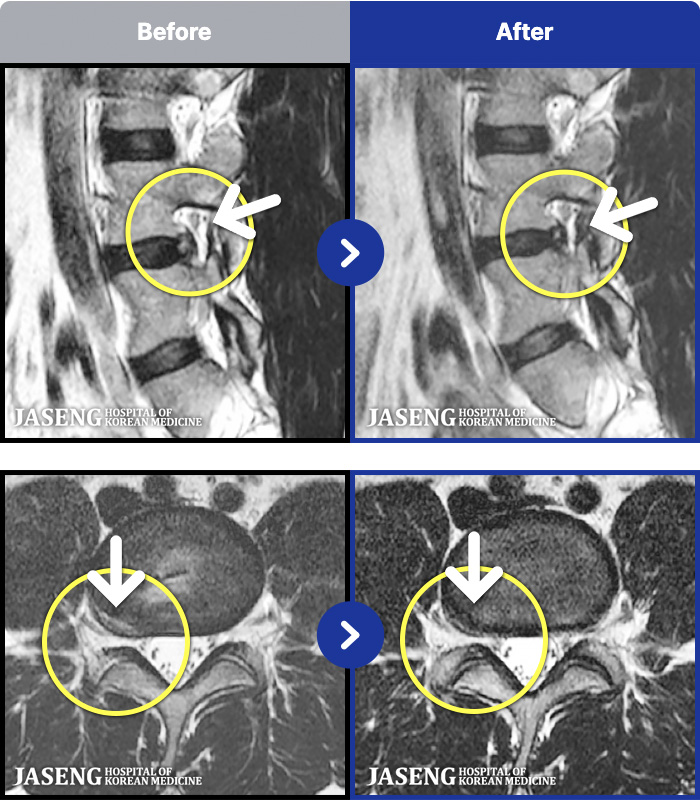

MRI ġ

1,240 MRI ũ ʸ Ȯϼ.